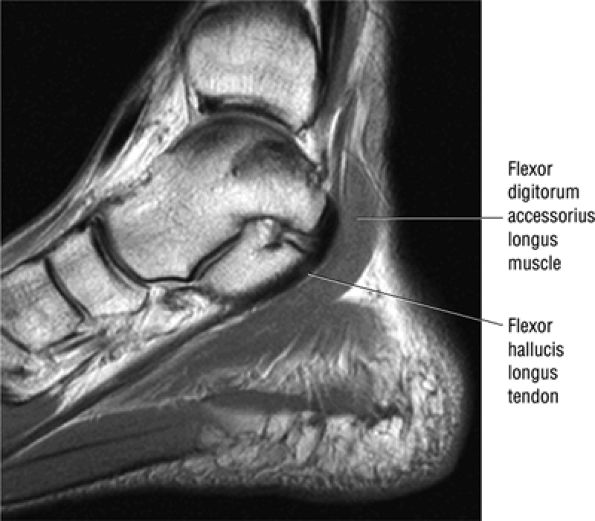

The flexor digitorum accessorius is an anomalous muscle located posterior to the FHL and has been associated with tarsal tunnel syndrome, although it is usually asymptomatic (Fig. 5.87).

FIGURE 5.87 ● The flexor digitorum accessorius longus muscle is located posterior to the flexor hallucis longus and courses through the tarsal tunnel with the posterior tibial neurovascular bundle.